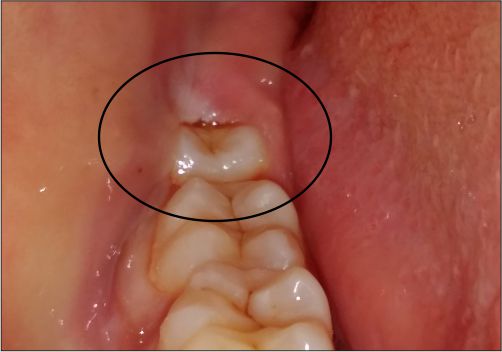

Preventive dentistry remains a cornerstone of any solid dental practice. Regular check ups and professional cleaning reduce the risk of decay, gum disease and future restorative needs. Clinics in Rajkot that focus on prevention typically provide fluoride treatments and sealants for children and adults. Scheduling biannual visits helps catch issues early, supporting long term oral health with minimal disruption to daily life. A practical clinic will tailor reminders and ongoing care plans to fit your schedule.

Dental treatments should aim for functional results that improve daily comfort and confidence. For those considering dental implants rajkot, the clinic should present a clear, evidence based plan outlining expectations, timelines, and aftercare. You deserve precise impressions, guided surgery options if available, and a discussion about maintenance to maximise the longevity of any prosthetic work. A patient centred approach ensures decisions align with lifestyle and budget while preserving natural tooth structure where possible.